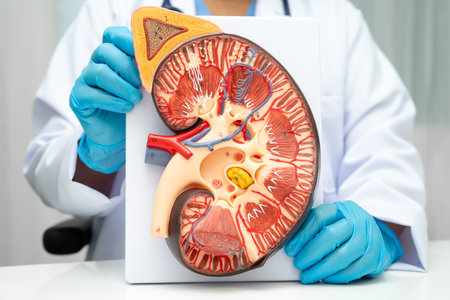

Kidney disease, Chronic kidney disease ckd, Doctor hold human model to treat and study in hospital.

Chronic kidney disease, doctor with model for treatment urinary system, urology, Estimated glomerular filtration rate eGFR.

Chronic kidney disease, doctor with model for treatment urinary system, urology, Estimated glomerular filtration rate eGFR.